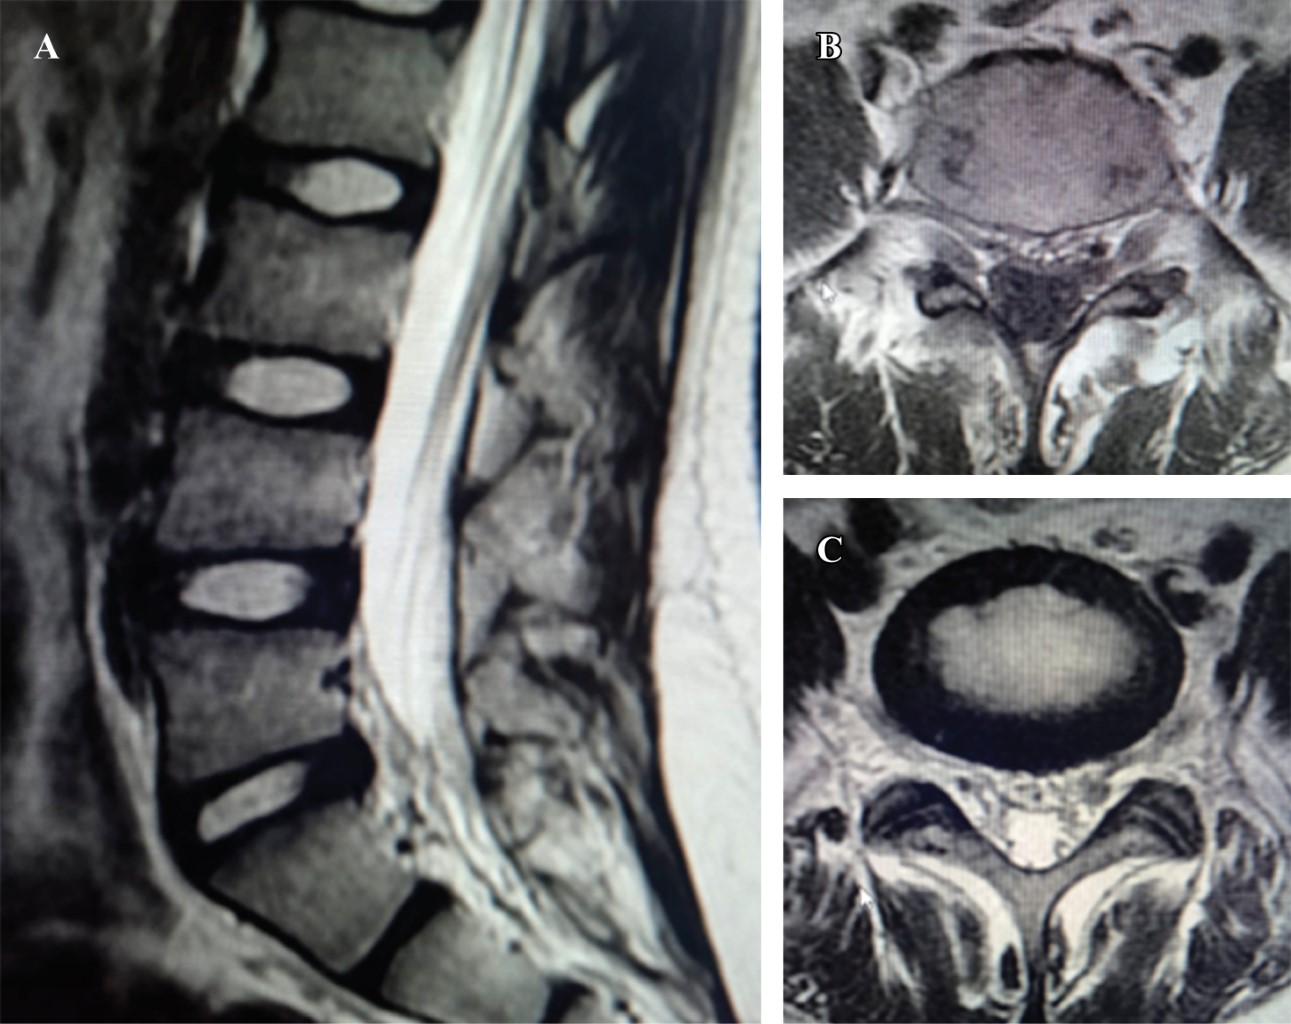

Se solicita resonancia magnética simple de columna lumbosacra en donde se observa en los cortes sagitales masa heterogénea hiperintensa dentro del conducto medular, inmediatamente posterior a disco intervertebral L5-S1 con extensión caudal a cuerpo vertebral subyacente S1 (Figura 1A). Corte axial en T1 y T2 se observa masa hiperintensa en la zona IV según Weinstein, ocupando aproximadamente 30% del conducto medular (Figuras 1B y 1C).

Figura 1